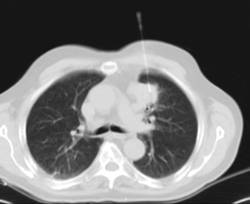

- Chest CT

Diagnostic test that provides high definition anatomical images of the chest (lungs, heart, mediastinum, great vessels, rib cage, etc.) using CT (Computed Tomography) equipment. These images are then examined on a workstation that allows bidimensional reconstructions in different planes of space and also 3D reconstructions (volumetric). Some studies require the use of an iodinated contrast agent to improve image definition.